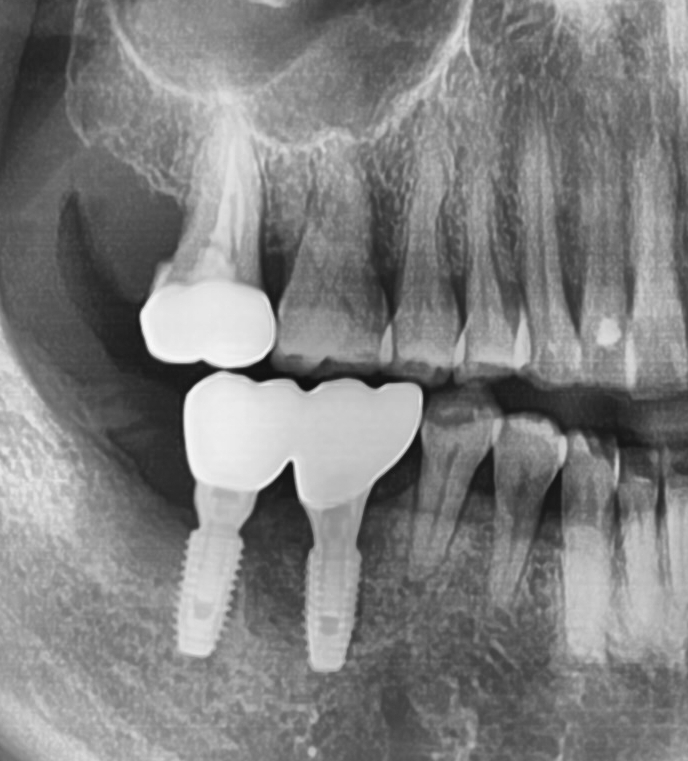

흔들리는 옆 치아와 흔들리는 임플란트를 제거하고 임플란트2개와 임플란트 브릿지로 마무리

흔들리는 옆 치아1개와 흔들리는 임플란트2개를 제거하고

3개의 자리를 임플란트2개와 가짜머리1개가 있는 임플란트 브릿지로

3개의 자리를 마무리하였습니다.